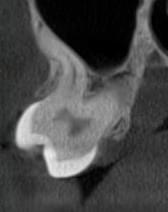

Успішна імплантація починається з бездоганної діагностики. Томограф PLANMECA забезпечує

зображення в реальному масштабі 1:1 без геометричних спотворень, що критично важливо для

вибору розміру та позиції імплантату.

Ми економимо ваш час, надаючи повний пакет передопераційної підготовки:

Детальна розмітка: промальовування нижньощелепного каналу, візуалізація синусів та

ментальних отворів.

Точні виміри: визначення висоти та ширини альвеолярного гребеня, а також оцінка щільності

кісткової тканини в зоні майбутньої операції.